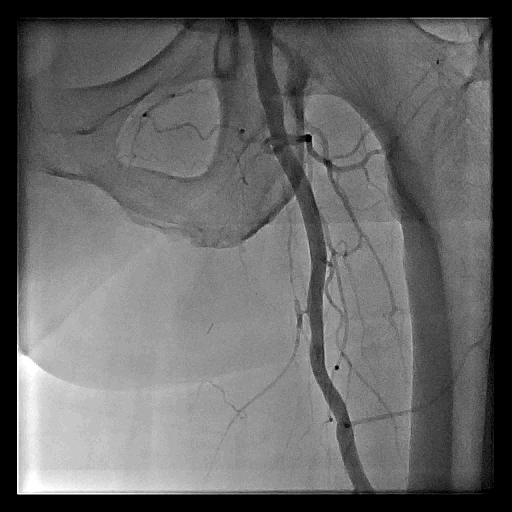

Figure 1. 淺股動脈的使用經皮腔內血管成形術治療

A. 右側淺股動脈慢性全閉塞

D. 打通右側淺股動脈